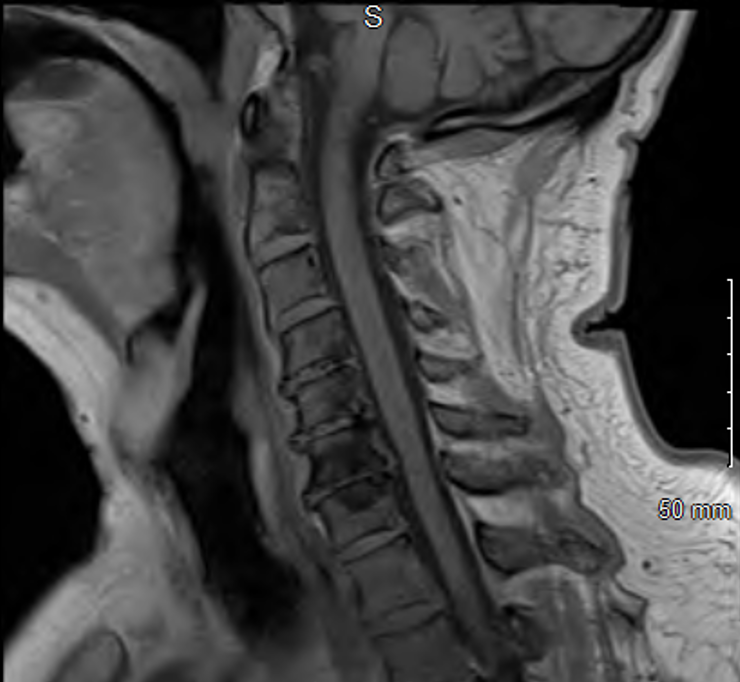

Figure 1. Neck MRI, sagittal view, showing no signs of compression

Initial workup with CBC, CMP, ESR, CRP, viral panel, head CT, MRI of the brain and neck were unremarkable. A video and barium swallow confirmed severe dysphagia and patient was kept NPO. Differentials included Miller Fisher Variant of Guillain-Barre Syndrome (GBS) and MG.